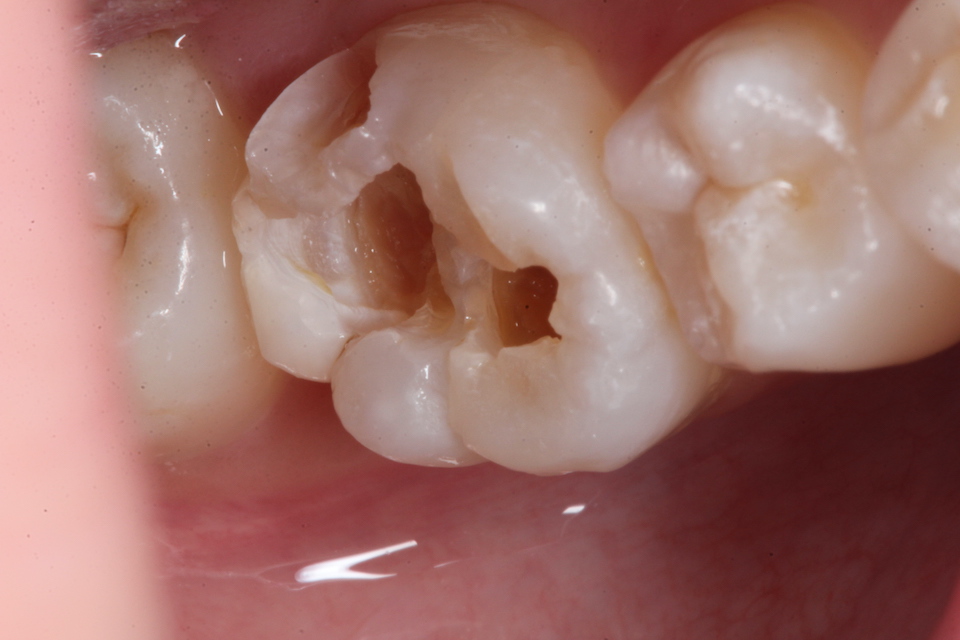

通常の歯科治療では神経を取って被せるということになるのだが、2次象牙質もできていて痛みもないのでそのままCRで再建した。

この方がトータルでは歯の寿命は長くなる。神経を取った歯は10年〜50年後には抜歯になってしまう。治療が上手くいっていても平均30年位か?

CR充填再建過程